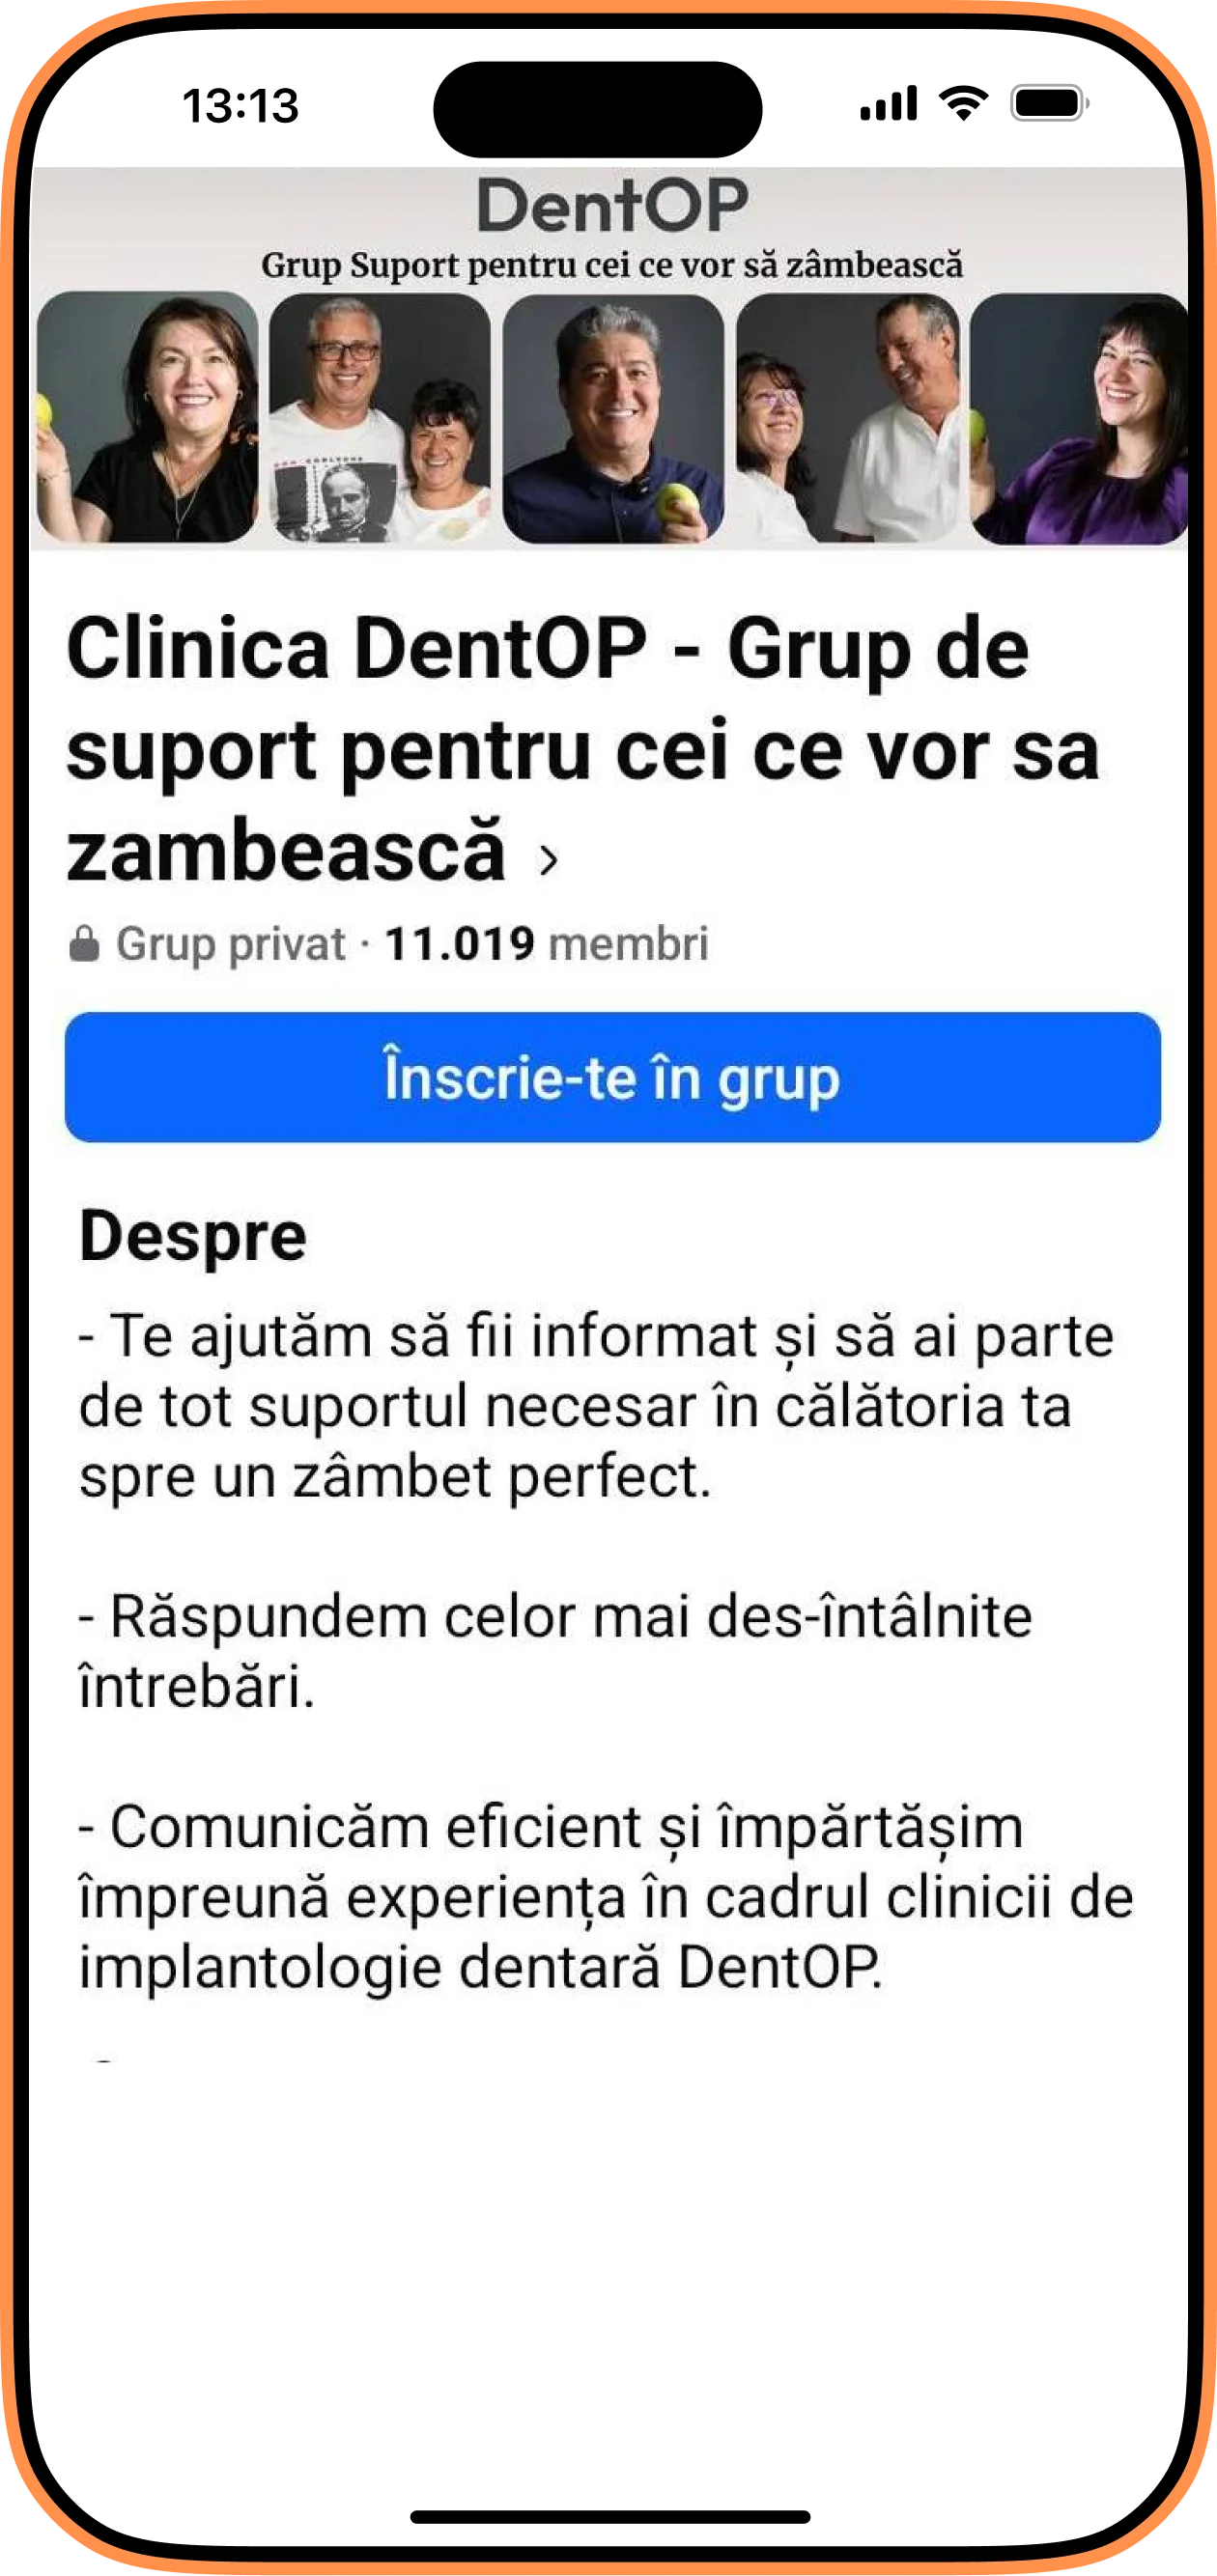

În radiografia de mai jos putem observa dantura inițială a domnului A.,iar apoi radiografia după inserarea celor 12 implanturi dentare.

După o analiză amănunțită a problemelor dentare și a stării generale de sănătate, Dr Cazacu Corrado, a decis un plan de tratament cu implanturi dentare. Pacientul nostru, fiind bine informat a confirmat planul propus de către Medicul Specialist Chirurgie Dento-Alveolară și astfel, dantura lui este acum una sănătoasă.

S-au inserat lucrări provizorii imediat după intervenție, iar pacientul le-a purtat timp de 6 luni, timp în care a avut grijă ca alimentația sa să fie una moale, protejând astfel vindecarea implanturilor.